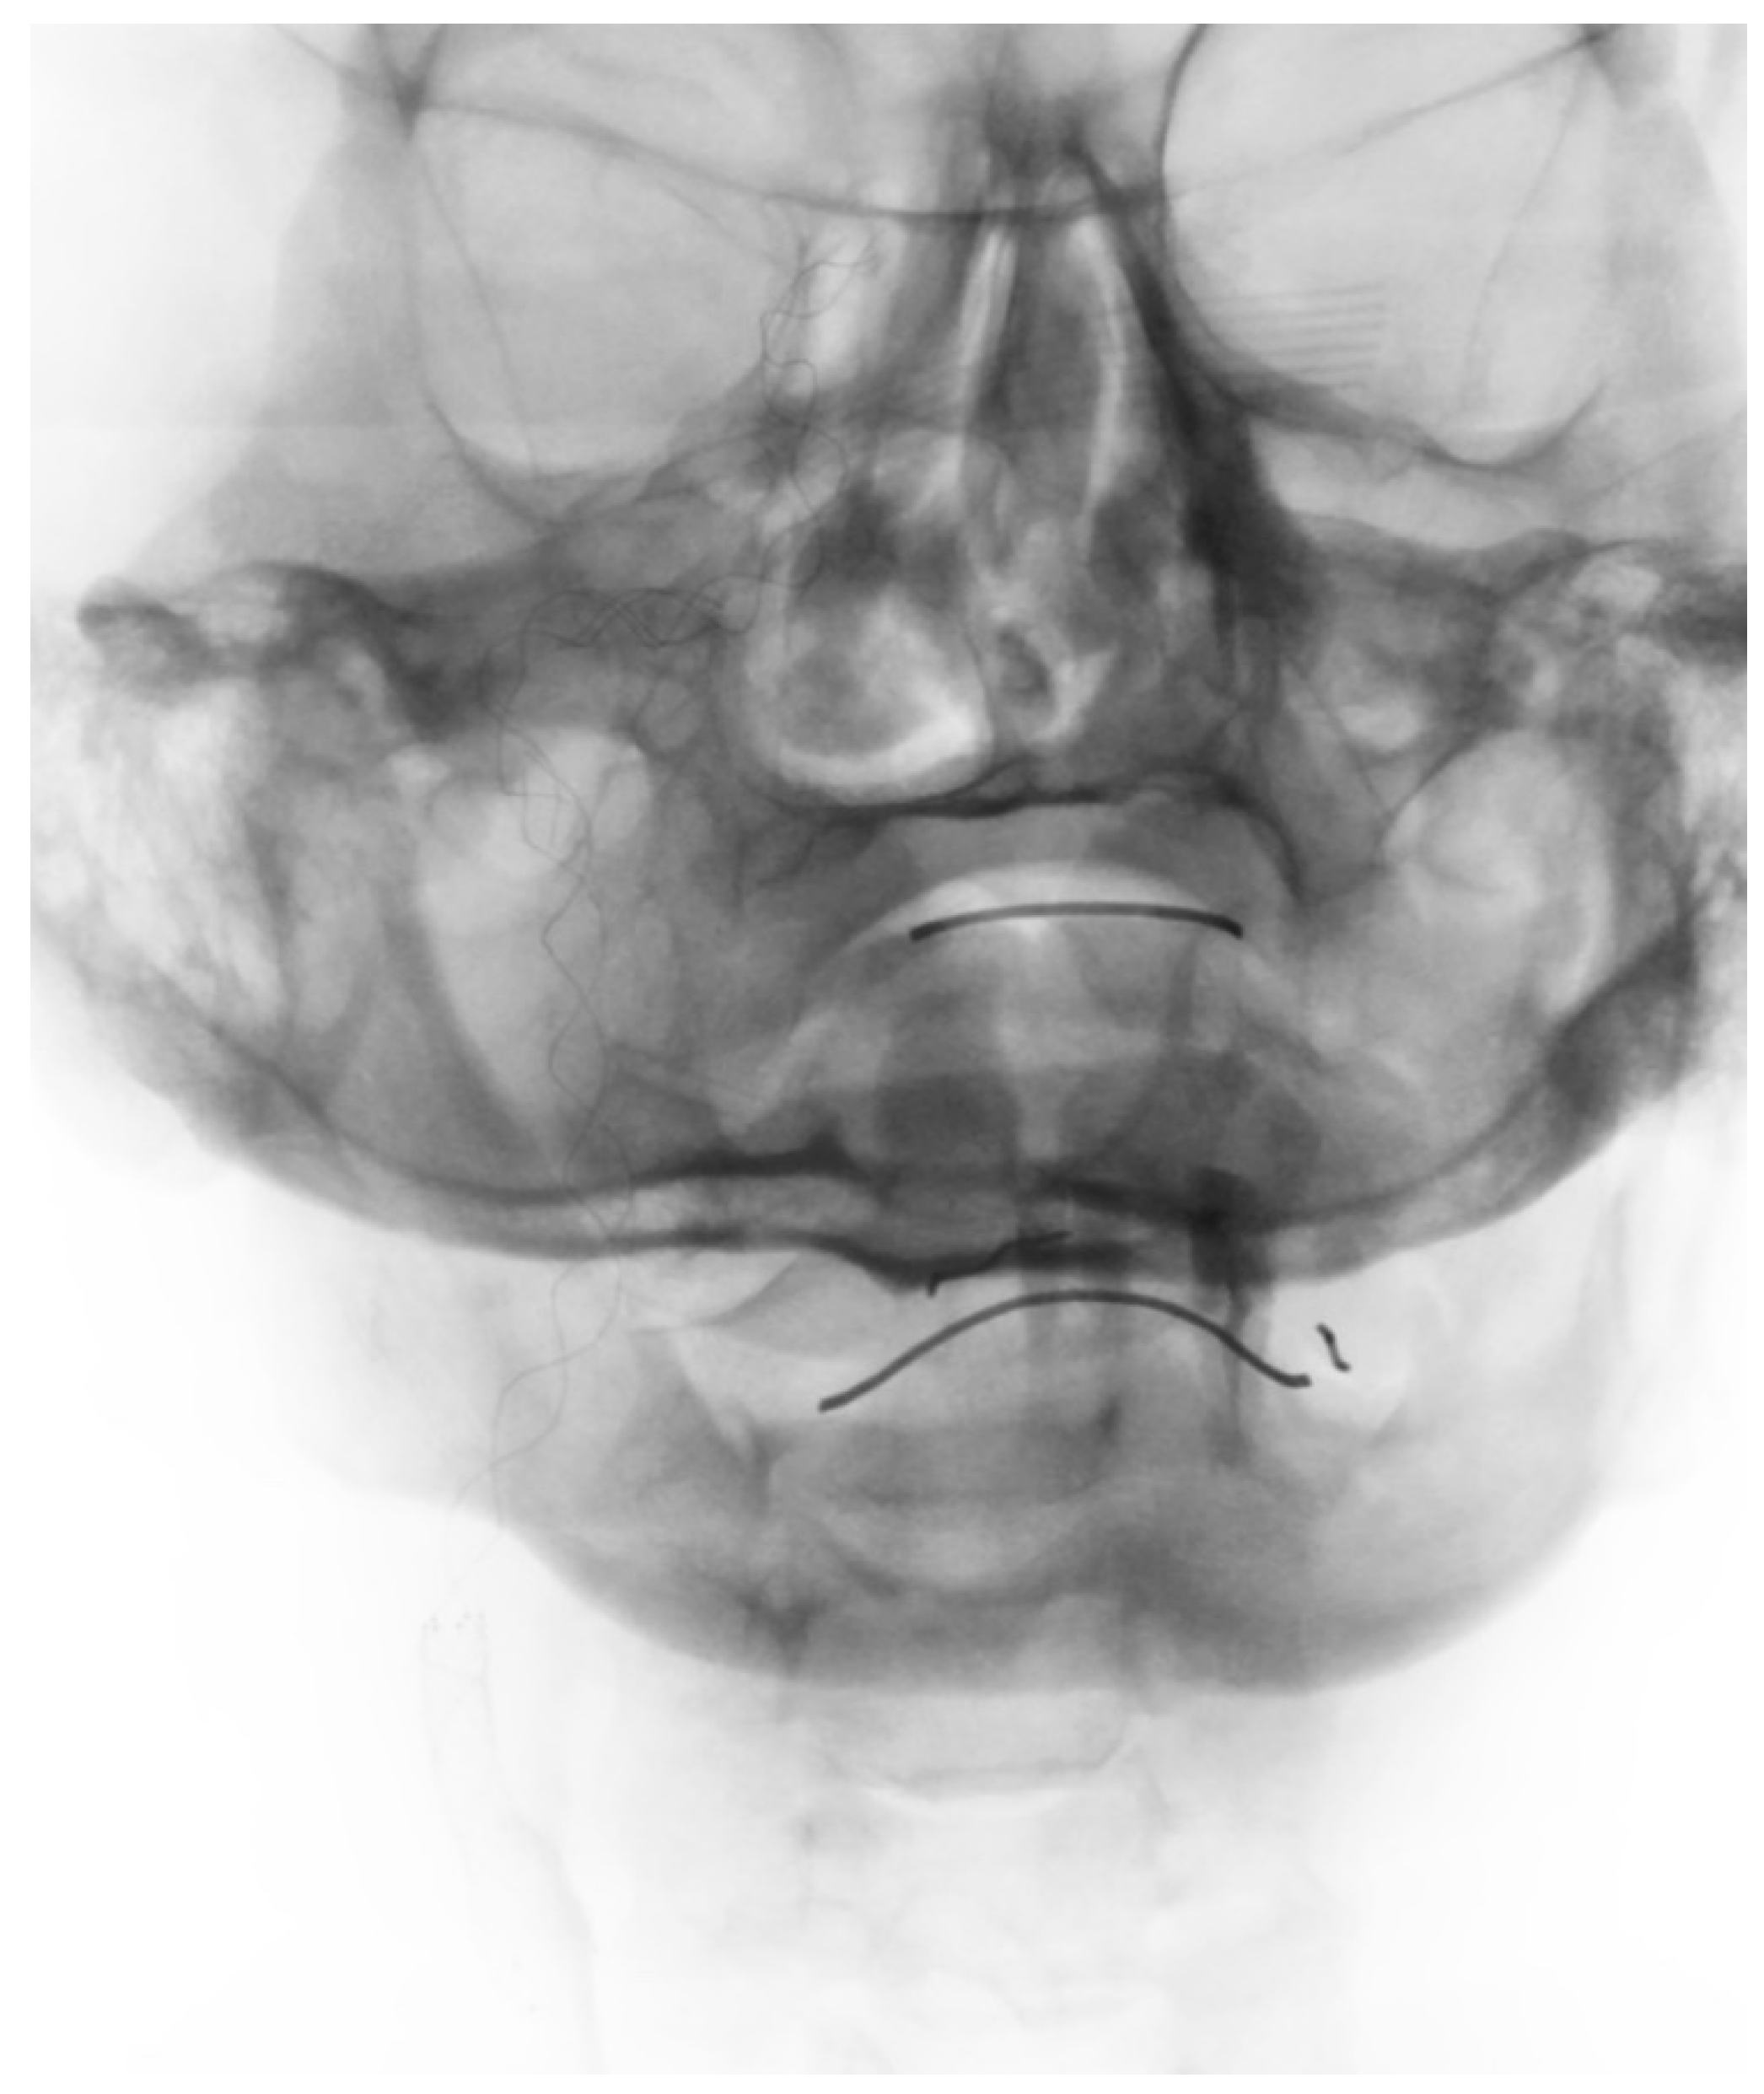

2. Case Presentation